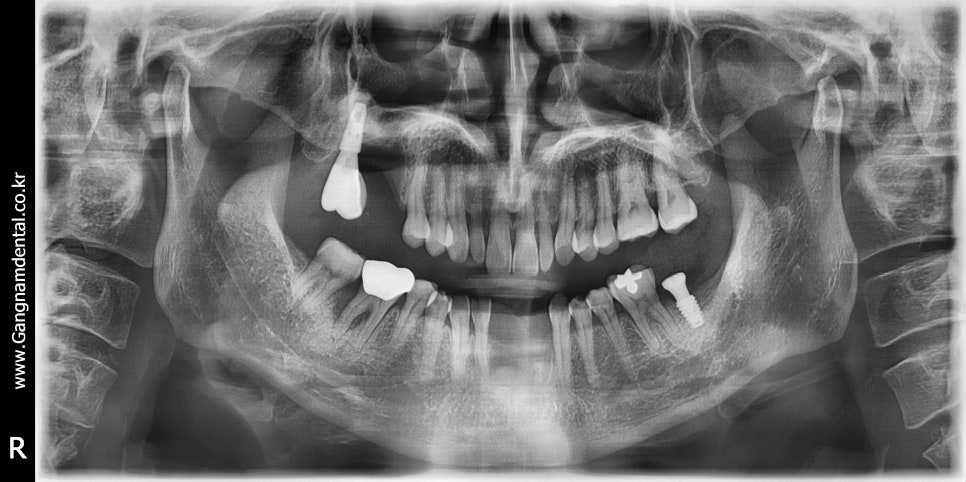

오늘은 37번에 임플란트를 심게 되었다. 사실 사랑니 발치 하려고 원장님 사랑니발치 교과서 1회독 한번 더 하고 올라왔는데, 내가 발치 예약 잡은 분이 코로롱 때문인지 오늘 못오신다고 그래서 발치는 못했다. 다음번엔 꼭 사랑니 발치 해야지..! 아무튼 그래도 저번에 36,37 임플란트 심어봤기 때문에 이번엔 나름 자신...

출처 아카이브 열기오늘은 37번에 임플란트를 심게 되었다. 사실 사랑니 발치 하려고 원장님 사랑니발치 교과서 1회독 한번 더 하고 올라왔는데, 내가 발치 예약 잡은 분이 코로롱 때문인지 오늘 못오신다고 그래서 발치는 못했다. 다음번엔 꼭 사랑니 발치 해야지..!

아무튼 그래도 저번에 36,37 임플란트 심어봤기 때문에 이번엔 나름 자신감과 이런저런 계획을 갖고 시작은 했지만, 성별의 차이때문이었는지 그냥 골질이 달라서 그런건지 그때랑은 또 달랐다.

전에 여성환자분께는 4.5파이 드릴링하고 4.5파이 수월하게 심었는데 이번엔 5.0드릴링 하고 5.0심는데도 빡빡하게 들어갔다. 5.5드릴을 절반정도만 담궈서 코로날부위만이라도 좀 쉐이핑을 하고 했으면 훨씬 나았을텐데 막상 지금 단계에 정신이 팔리니 배운것도 잘 못써먹더라. 픽스쳐가 빡빡하게 들어가니 환자분께서도 좀 불편해하셨다.

방향은 만족스러웠고 다만 픽스쳐 길이와 깊이에 아쉬움이 좀 남는다. 36distal bone에 스타퍼가 걸리는 문제 때문에 총 1시간이 넘게 걸렸고 환자분께서 아파하셔서 드릴링을 또 한번 하기가 내 마음이 아파서 픽스쳐 길이 안바꾸고 5mm 힐링 달고 마무리 했다. 사실 중간에 4.5 심었는데 7mm힐링 달았더니 김영삼원장님께서 보시곤 7mm빼고 5mm로 하라고 하셔서, 7mm힐링 풀다가 (조일 때 너무 꽉 쪼여놔서)픽스쳐도 같이 빠지긴 했는데~ 그 덕에 4.5에서 5.0으로 쉽게 바꿨다ㅋㅋ;; 한단계 덜어줬다..ㅋㅋㅋ...ㅋㅋ🤣